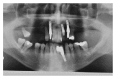

Purpose. Implant therapy plays an important role in contemporary dentistry with high rates of long-term success. However, in recent years, the incidence of peri-implantitis and implant failures has significantly increased. The peripheral giant cell granuloma (PGCG) rarely occurs in peri-implant tissues and it is clinically comparable to the lesions associated with natural teeth. Therefore, the study of possible diseases associated with dental implants plays an important role in order to be able to diagnose and treat these conditions. Materials and Methods. This report described a 60-year-old Caucasian male who presented a reddish-purple pedunculated mass, of about 2 cm in diameter, associated with a dental implant and the adjacent natural tooth. Results. An excisional biopsy was performed and the dental implant was not removed. Histological examination provided the diagnosis of PGCG. After 19-month follow-up, there were no signs of recurrence of peri-implantitis around the implant. Conclusion. The correct diagnosis and appropriate surgical treatment of peri-implant giant cell granuloma are very important for a proper management of the lesion in order to preserve the implant prosthetic rehabilitation and prevent recurrences.